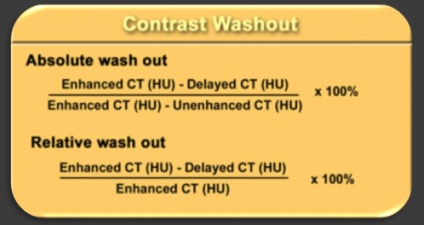

10% -40% au puțină grăsime (≥10HU), astfel adenoamelor numita "lipid-săraci" și sunt considerate nesigure, este opacifierea necesar (după 1 min și 15 min).

Cele mai multe 3-5cm, rotunjite, 35,9 HU ± 9,8 (CT nativ), 10% au calcificări pot fi fibroza, chist, includerea de grăsime, homo- il eterogenă.

F. variabilă - „imagine cameleon“. Se recomandă să se includă f. în leziunile DD cu densitate scăzută, washout HF rapidă, leziuni chistice cu componenta dominantă, în funcție de parametrii clinici și de laborator.

Mărimea, structura, parametrii de densitate în leșiere nativă și HF, comportamentul izotop, rezultatele cercetarii pentru a gasi boala metastatică.

- Până la 4 cm mai jos 10hu. eluare 60% deplasare chimică MR. - adenom?